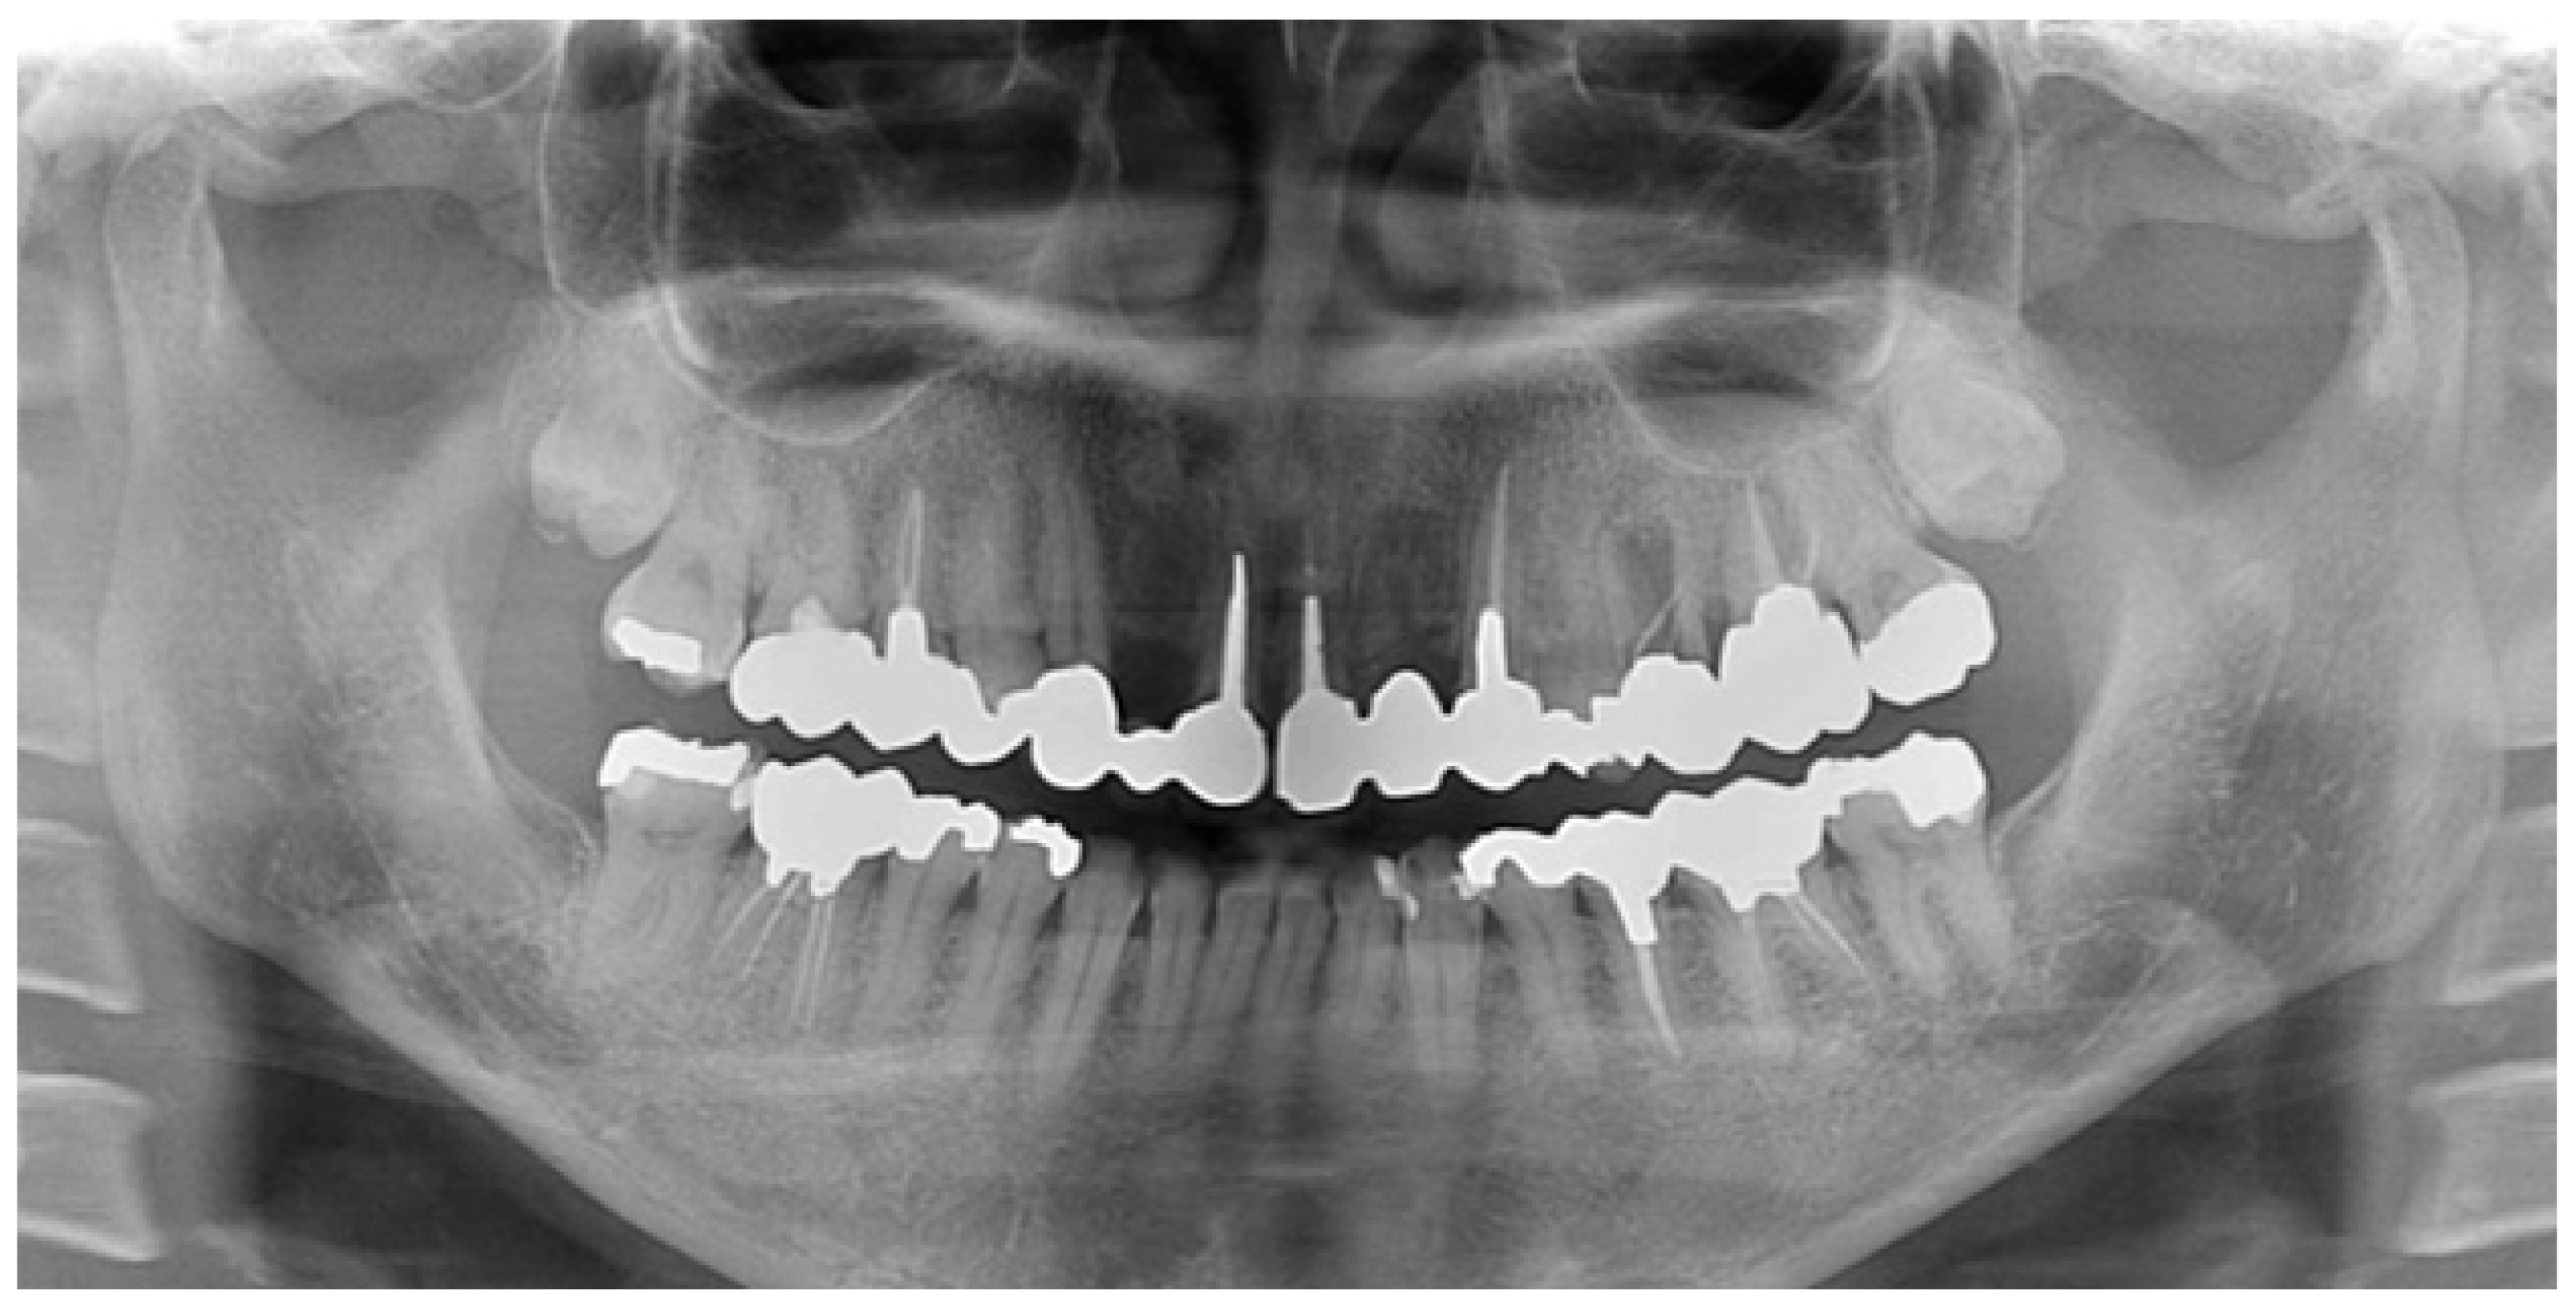

| 1 | Initial visit (August 2015) | Initial assessment & provisionalization | Assessment after traumatic event; long-span provisional restoration to re-establish posterior support and stabilize occlusion (Figure 1 and Figure 2) |